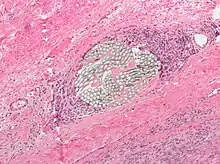

Foreign bodies in the peritoneum eventually become contained in a foreign body granuloma. In the extremely rare case of retained ectopic pregnancy, this forms a lithopedion, which involves the fetus being too large to be reabsorbed, and is calcified[13] as a means of shielding the surrounding tissue from infection.